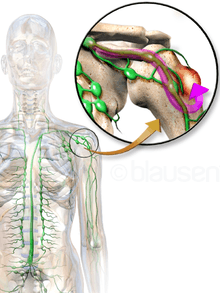

Bone metastases, or metastatic bone disease, is a class of cancer metastases that results from primary tumor invasion to bone. Bone-originating primary tumors such as osteosarcoma, chondrosarcoma, and Ewing's sarcoma are rare.[1] Unlike hematological malignancies that originate in the blood and form non-solid tumors, bone metastases generally arise from epithelial tumors and form a solid mass inside the bone. Bone metastases cause severe pain, characterized by a dull, constant ache with periodic spikes of incident pain.[2]

Bone is the third most common location for metastasis, after the lung and liver.[5] While any type of cancer is capable of forming metastatic tumors within bone, the microenvironment of the marrow tends to favor particular types of cancer, including prostate, breast, and lung cancers.[3] Particularly in prostate cancer, bone metastases tend to be the only site of metastasis.[2] The most common sites of bone metastases are the spine, pelvis, ribs, skull, and proximal femur.[6]